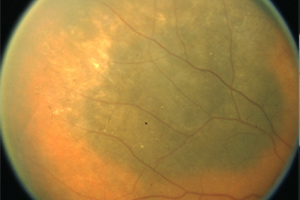

Fundusfotographie

Mit einer Funduskamera, einer speziell für die Netzhautfotografie entwickelte Kamera, werden Veränderungen an der Netzhaut zur Sicherheit fotografisch untersucht und dokumentiert. Wegen der hohen Auflösung und je nach Aufnahmewinkel ermöglicht sie präzise Aufnahmen insbesondere des Sehnerven, der Netzhaut, der Blutgefäße und der Aderhaut. Spezielle Filter liefern dabei Informationen, die bei der einfachen augenärztlichen Untersuchung verborgen bleiben. Der Vergleich von Aufnahmen, die zu unterschiedlichen Zeitpunkten aufgenommen wurden, ermöglicht eine genaue Beobachtung von Krankheitsverläufen. Bei Veränderungen kann somit zeitnah eine entsprechende Therapie oder Therapieanpassung vorgenommen werden.

Was passiert bei der fotografischen Untersuchung?

Bei weitgestellter Pupille (Achtung: keine Fahrtauglichkeit für mindestens 4 Stunden nach der Untersuchung!) werden mit Hilfe eines Auslösers nacheinander mehrere Bilder von der Netzhaut angefertigt. Die Untersuchung ist berührungsfrei und dauert nur wenige Minuten.

Was kann ich von der fotografischen Dokumentation erwarten?

Durch die Farbfotografien können wir sehr viel genauer das aktuelle Stadium der Erkrankung mit den Ergebnissen der vorangegangenen und künftiger Untersuchungen vergleichen. Selbst kleine Veränderungen lassen sich zuverlässig beurteilen. Am Computerbildschirm können wir Ihnen die Befunde im Anschluss an die Untersuchung nachvollziehbar erläutern und – wenn es erforderlich ist – gemeinsam mit Ihnen das weitere therapeutische Vorgehen besprechen.

Darstellung des Augenhintergrundes (Fundus) ohne krankhaften Befund

Die Veränderung des Fundus bei einem krankhaften Befund (Tumor)